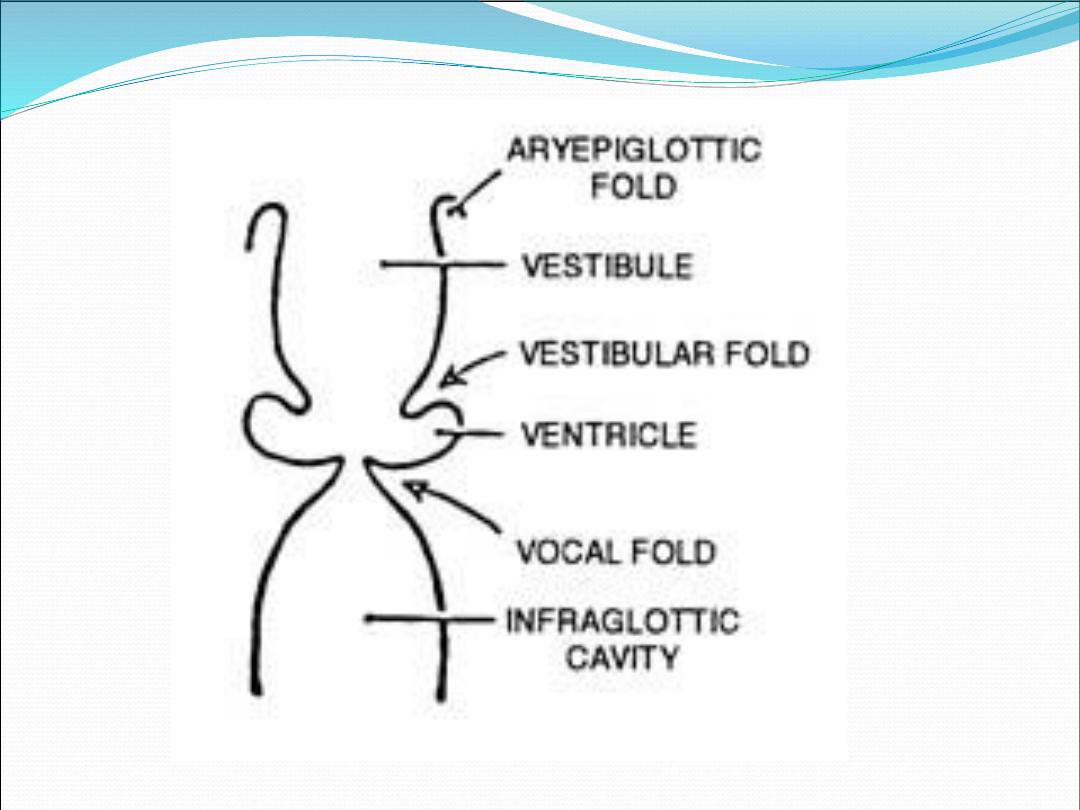

Supraglottis

1.

Epiglottis

2.

Aryepiglottic folds

3.

Arytenoid

4.

Ventricle

1.

Anterior and posterior commissures

2.

True vocal cords

Subglottis

Extend from the under surface of the vocal cords

to the inferior edge of cricoid cartilage